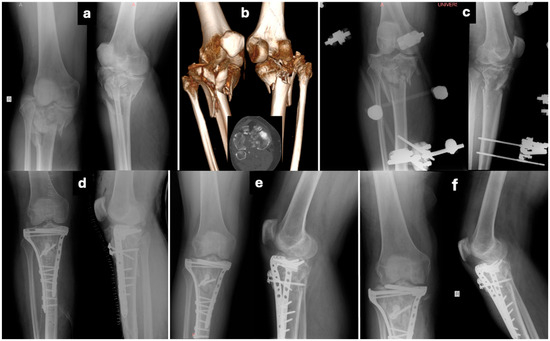

Comparative Outcomes of Single- Versus Dual-Incision Approaches for Open Reduction and Internal Fixation of Complex Tibial Plateau Fractures

Background/Objectives: Open reduction and internal fixation with plates and screws is the treatment of choice for bicondylar tibial plateau fractures. The use of a surgical approach remains a topic of debate regarding the site and number of incisions that ensure best access [...] Read more.

Background/Objectives: Open reduction and internal fixation with plates and screws is the treatment of choice for bicondylar tibial plateau fractures. The use of a surgical approach remains a topic of debate regarding the site and number of incisions that ensure best access for reduction with minimum additional soft tissue damage. This retrospective cohort study compared clinical, radiological, and functional outcomes of single- (anterior) versus dual-incision (anterolateral and medial) approaches that are widely used in the operative treatment of Schatzker V–VI tibial plateau fractures. Methods: Eighty-two patients treated between 2005 and 2020 were retrospectively analyzed. Fifty-two underwent a single-incision (SI) approach and 30 a dual-incision (DI) approach. Operative parameters, complications, reduction quality, Knee Society Score (KSS), Oxford Knee Score (OKS), and post-traumatic arthritis incidence were assessed. Results: Mean patient age was 50.6 years, with a mean follow-up of 8.5 years. Operative time was shorter in the SI group, though fluoroscopy time was longer. No significant difference was observed in reduction quality or wound complications. Post-traumatic arthritis occurred in 57.6% of SI and 53.3% of DI patients, with severe arthritis more frequent in SI (30% vs. 12.5%, p < 0.05). Seven patients required conversion to total knee arthroplasty (five SI, two DI). Functional recovery was similar: mean KSS 68.6% (SI) vs. 70.5% (DI) and OKS 36.1 vs. 40.8 (p > 0.05) at 5 years. Conclusions: Both single- and dual-incision approaches for complex tibial plateau fractures provide satisfactory long-term outcomes. While differences in complications and arthritis rates were minor, surgical choice should be guided by the fracture morphology, patient characteristics, and surgeon’s experience to balance reduction quality with soft tissue preservation. Full article

Show Figures

Figure 1